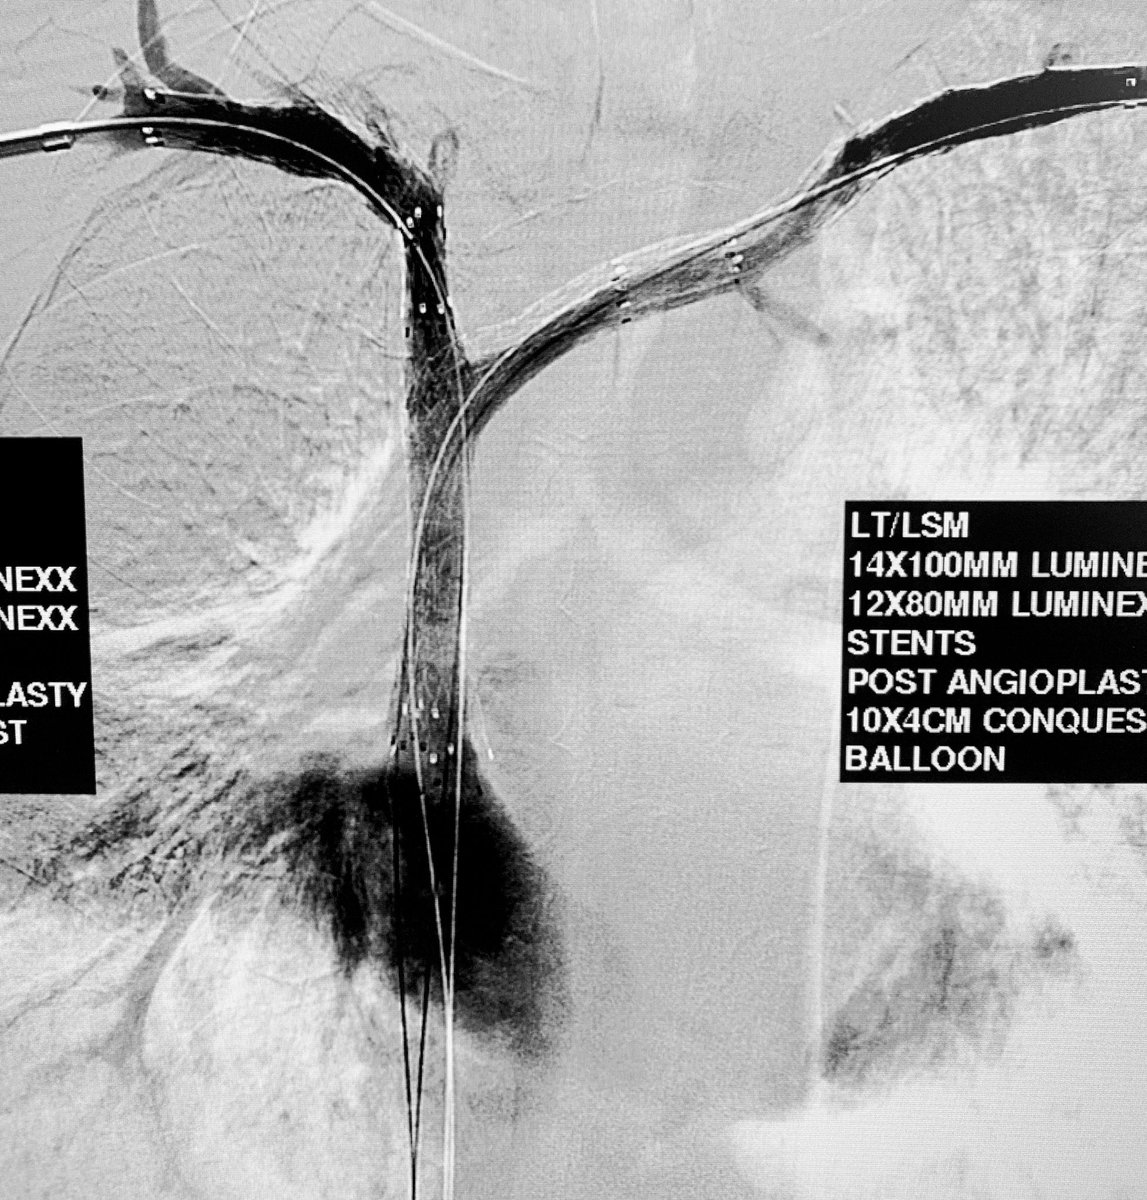

#venousreconstruction for b/l#legswelling.#IVC#occlusion from#filter placed 6 months ago for DVT and brain bleed. 2 IR effort ( Dr. Gordon).#filterretrieval followed by#iliocaval#stenting with#venovo.#irad#twittIR@SIRspecialists@SIR_ECS@SIRRFS@JVIRmedia@PairsWebpic.twitter.com/PqlCM1BJxL